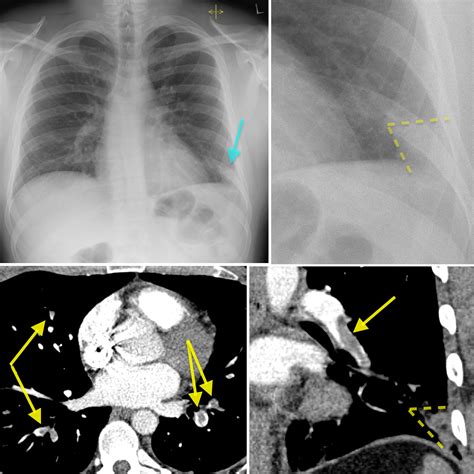

Key findings on a Pulmonary Embolism X Ray that may suggest PE include:

• Wedge-shaped opacities: These are areas of increased density in the lung tissue, often seen in the periphery of the lung.

• Pleural effusion: Fluid accumulation in the pleural space, which can be a sign of inflammation or infection.

• Enlarged pulmonary arteries: Dilatation of the pulmonary arteries, which may indicate increased pressure due to a clot.

• Atelectasis: Collapse or incomplete expansion of the lung tissue, which can be a sign of obstruction.

However, it is important to note that these findings are not specific to PE and can be seen in other conditions. Therefore, further diagnostic testing is often required to confirm the diagnosis.